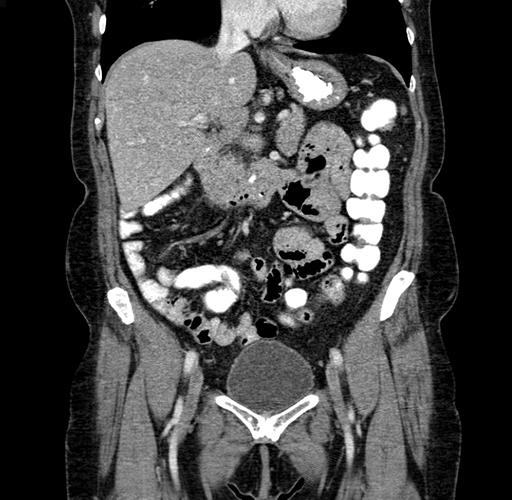

Pre-Chemo: Coronal Venous